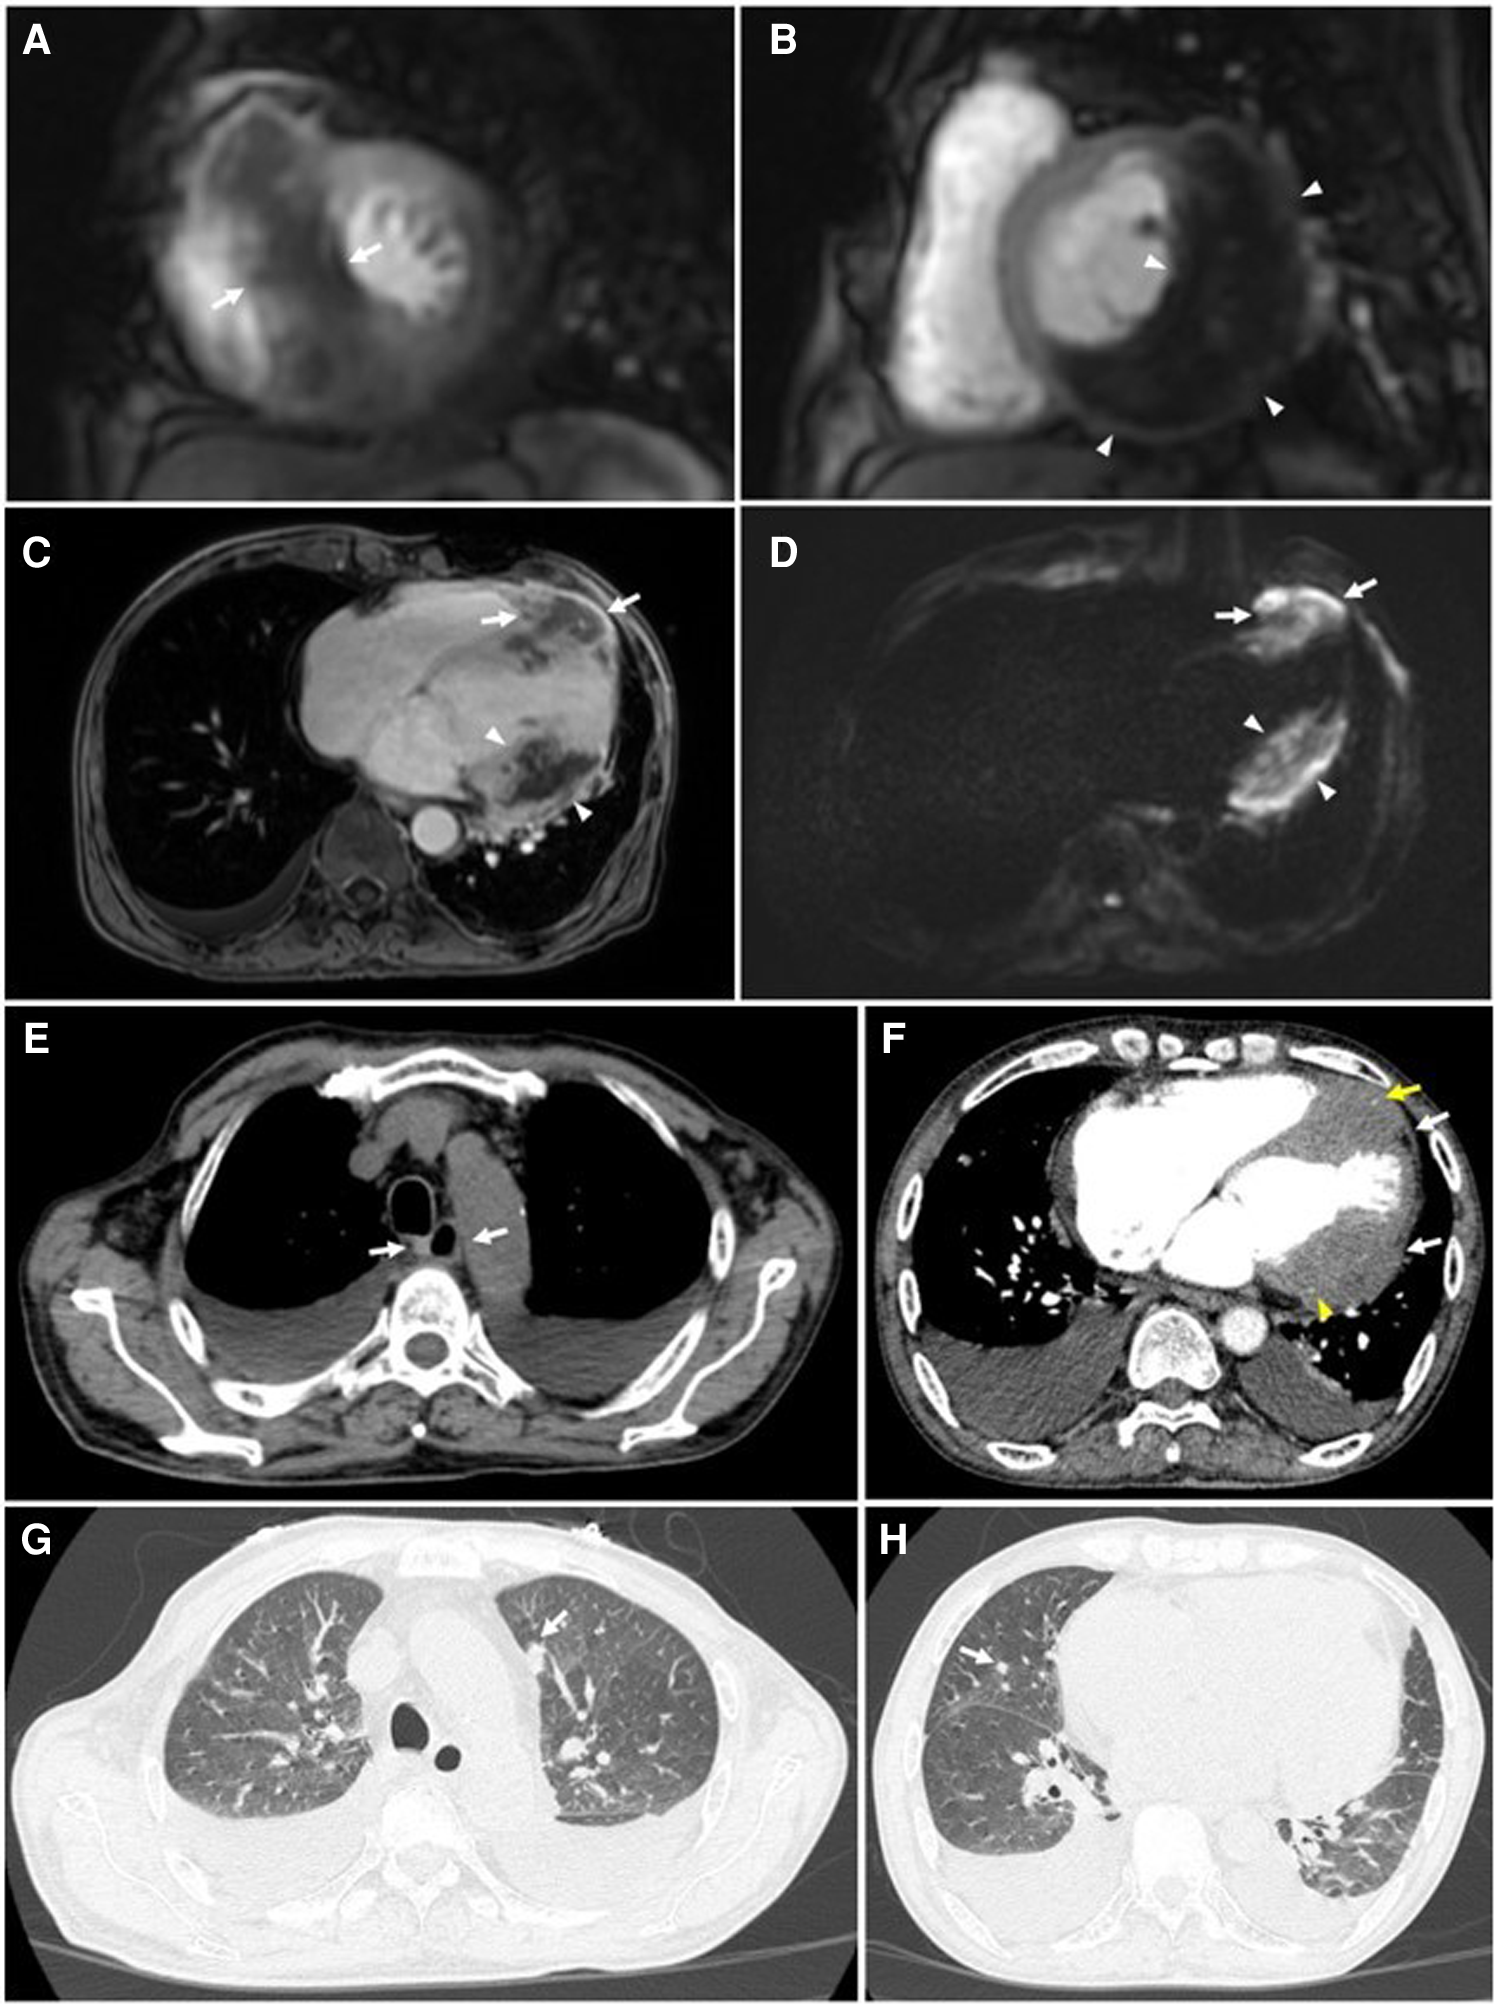

Figure 3

Cardiac magnetic resonance and thoracic computed tomography were obtained 6 months after completion of chemoradiotherapy. CMR: (A to D) Tumors of the interventricular septum (white arrows) and inferior-lateral left ventricular wall (white arrowheads) do not demonstrate enhancement on short-axis first-pass perfusion images (A & B) and axial post-contrast T1-weighted images (C) suggestive of necrosis. These lesions demonstrate restricted diffusion on the axial diffusion-weighted images (DWI) (D). (E) No abnormal thickening of the esophageal wall is seen on the mediastinal window (white arrows). (F) Tumors of the interventricular septum and inferior-lateral left ventricular wall invade the left anterior descending (LAD) artery (yellow arrows) and left circumflex (LCx) artery (yellow arrowheads), respectively. These lesions also extend to the pericardium (white arrows). (G & H) Metastatic nodules in the upper lobe of the left lung and the middle lobe of the right lung are seen on the lung window (white arrows).

On thoracic MDCT, the mediastinal window showed infiltrative lesions causing abnormal wall thickening of the interventricular septum toward the apex, as well as of the inferior, posterior, and lateral walls of the left ventricle corresponding to the lesions observed on TTE. These lesions extended beyond the myocardium to the pericardial fat. The left anterior descending (LAD) artery and the left circumflex (LCx) artery were encased completely and compressed mildly. The adjacent pericardium was irregularly thickened (Figure 3F). These lesions were new in comparison with the pre-treatment film (Figure 4C). The ESCC was significantly diminished, and there was no longer abnormal esophageal wall thickening (Figures 4A, B; Figure 3E). On lung window, two new well-defined solid nodules in the left upper lobe and the right middle lobe were detected (Figures 3G, H) compared to before treatment (Figure 4D). On CMR, two tumors enhanced mildly on first pass perfusion images but had peripheral heterogeneous enhancement in post-contrast T1-weighted images with central necrosis. In addition, the tumors appeared to have restricted diffusion on the diffusion-weighted imaging (DWI) (Figure 3 A to D).